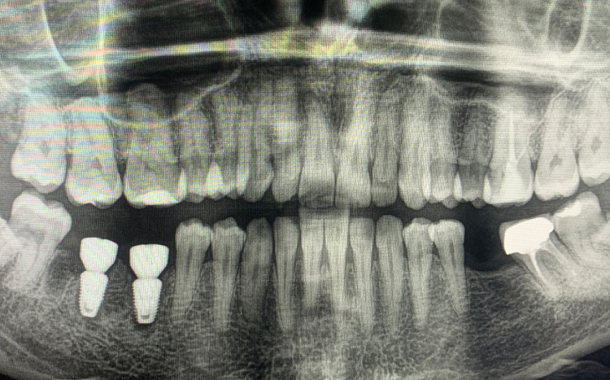

По 3D компьютерной томографии определяет возможность установки имплантата, немедленной фиксации временной коронки в день операции и объем пластических манипуляций. Совместно с врачом-стоматологом ортопедом планирует вид ортопедической конструкции и положение имплантата.

Компьютерная томография в формате 3D - важный диагностический инструмент стоматолога. На полученном объемном снимке стоматолог видит все нюансы вашей зубочелюстной системы: состояние костной ткани челюстей, зубов и височно-нижнечелюстного сустава. Именно томография позволяет доктору составить план и объем предстоящего оперативного вмешательства.

Обязательным условием подготовки к имплантации является снятие слепков и изготовление диагностических моделей для планирования и изготовления временной ортопедической конструкции, а в определенных условиях хирургического шаблона. Хирургический шаблон — накладка из пластмассы на зубной ряд с отверстиями для имплантатов. Благодаря шаблону хирург Немецкого Стоматологического Центра устанавливает имплантат в заранее спланированное положение, не нарушая траекторию ни на миллиметр.